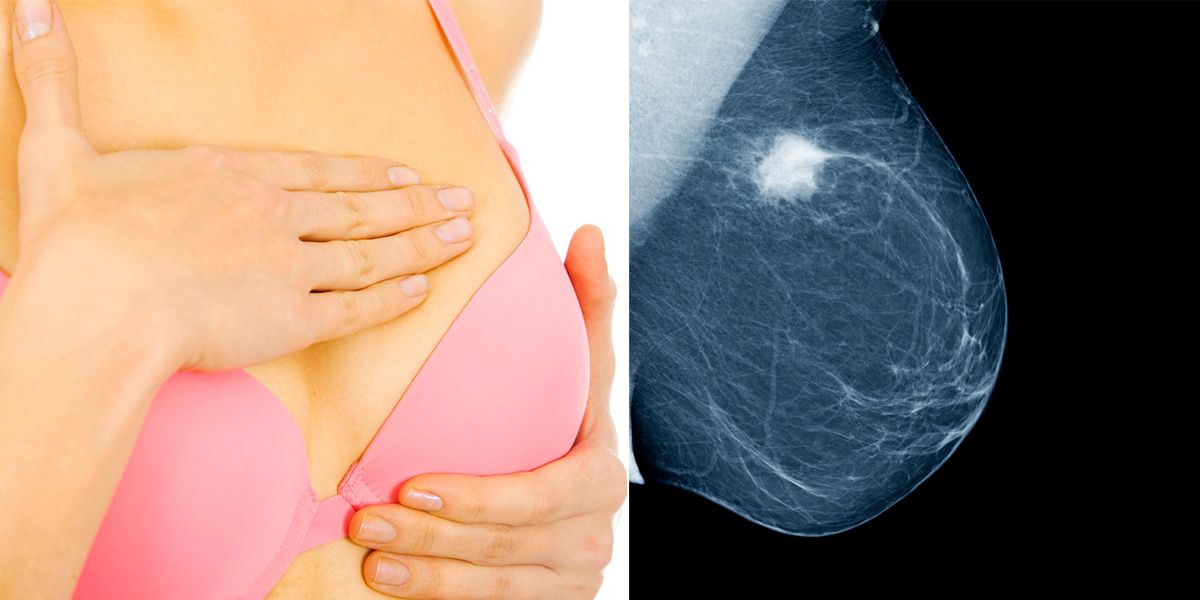

Brustkrebs ist weltweit eine der häufigsten Erkrankungen. Wenn man ihn frühzeitig erkennt (Stichwort Brustkrebsvorsorge!), sieht die Prognose gut aus. Dennoch bleibt immer ein Restrisiko, dass der Krebs zurückkehrt. Ein neuer Bluttest kann jetzt vorhersagen, ob Brustkrebs zurückkehren wird – bis zu 3,5 Jahre früher, bevor er sich auf Scans zeigt. So kann die Behandlung beginnen, bevor er unheilbar wird.

Der "ultraempfindliche" Test kann Spuren der DNA eines Tumors aufspüren, bevor ein kompletter Rückfall auftritt, bei dem die Behandlung weitaus schwieriger ist. Mit einer 100-prozentigen Genauigkeit kann der Test vorhersagen kann, bei welchen Patienten der Krebs zurückkehren wird.